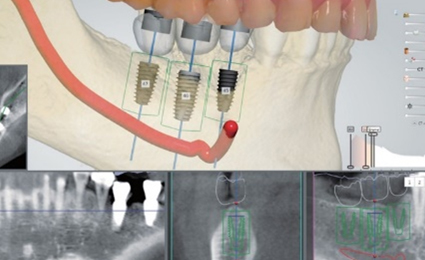

디지털 임플란트의 편안함

빠르고 체계적인 임플란트

우리에게 올바른 길을 알려주는 네비게이션처럼

디지털 기술을 통해 최적의 수술 경로를 알려주는

디지털 분석 임플란트.

3D 모의 수술을 통해 식립 위치를 정밀하게 파악하고

오차 가능성을 줄인 체계적인 임플란트 입니다.

디지털 분석 임플란트의 편안함

-

골조직, 신경위치 자세히 분석하여 올바른 위치 선정

한번에 여러개 치아 수술 가능

최소통증, 최소출혈 최소 절개 시술로 빠른 회복